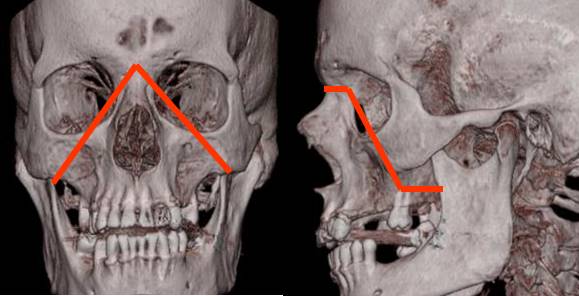

Fig 221. Diagrama de Lefort I.

Fractura horizontal del hueso maxilar.

Fig 223. Diagrama de Lefort II.

Fractura en forma  piramidal, con ápex en la sutura nasofrontal y base en los dientes. Compromete el borde interno, piso de la órbita y el hueso malar.

Fig 225. Diagrama de Lefort III.

Fractura donde se separa la cara del cráneo. Compromete la sutura nasofrontal, borde interno y externo de la órbita y el arco cigomático.